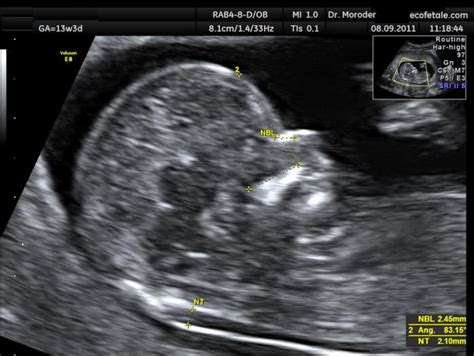

- Ecografia fetale: Oltre alla misurazione dello spessore della translucenza nucale - la raccolta di liquido retronucale presente in tutti i feti tra 11 e 13 settimane, ma che risulta aumentata nell'80% dei feti affetti da Sindrome di Down - l'ecografia permette anche la valutazione di altri parametri di crescita fetale e, in molti casi, la ricerca della presenza dell’osso nasale. La sua assenza o ipoplasia (sviluppo incompleto) può essere un ulteriore indicatore di rischio per alcune anomalie cromosomiche.

L'esame richiede l'uso di apparecchiature ecografiche di alta tecnologia, capaci di fornire immagini chiare e dettagliate del feto in una fase così precoce dello sviluppo. Durante l’esame, il medico ginecologo o l’ecografista specializzato si concentra non solo sulla misurazione dello spessore della translucenza nucale, ma valuta anche l’anatomia fetale ecograficamente indagabile. Questo include la verifica della presenza dell’osso nasale e di altri indicatori morfologici utili a individuare eventuali anomalie cromosomiche o strutturali.

L'intervallo di esecuzione consigliato per questo importante controllo ecografico si situa tra la 11^ settimana e la 14^ settimana di gestazione. Tuttavia, per il "primo incontro" che può includere anche il prelievo ematico per il Bi-Test, un intervallo leggermente più ampio può essere considerato, ovvero tra la 9^ settimana + 1 giorno di gestazione e la 11^ settimana + 3 giorni di gestazione per il prelievo e, a seguire, la valutazione ecografica completa. La precisione della misurazione è influenzata anche dalle dimensioni del feto, motivo per cui la finestra temporale di esecuzione è così specifica.